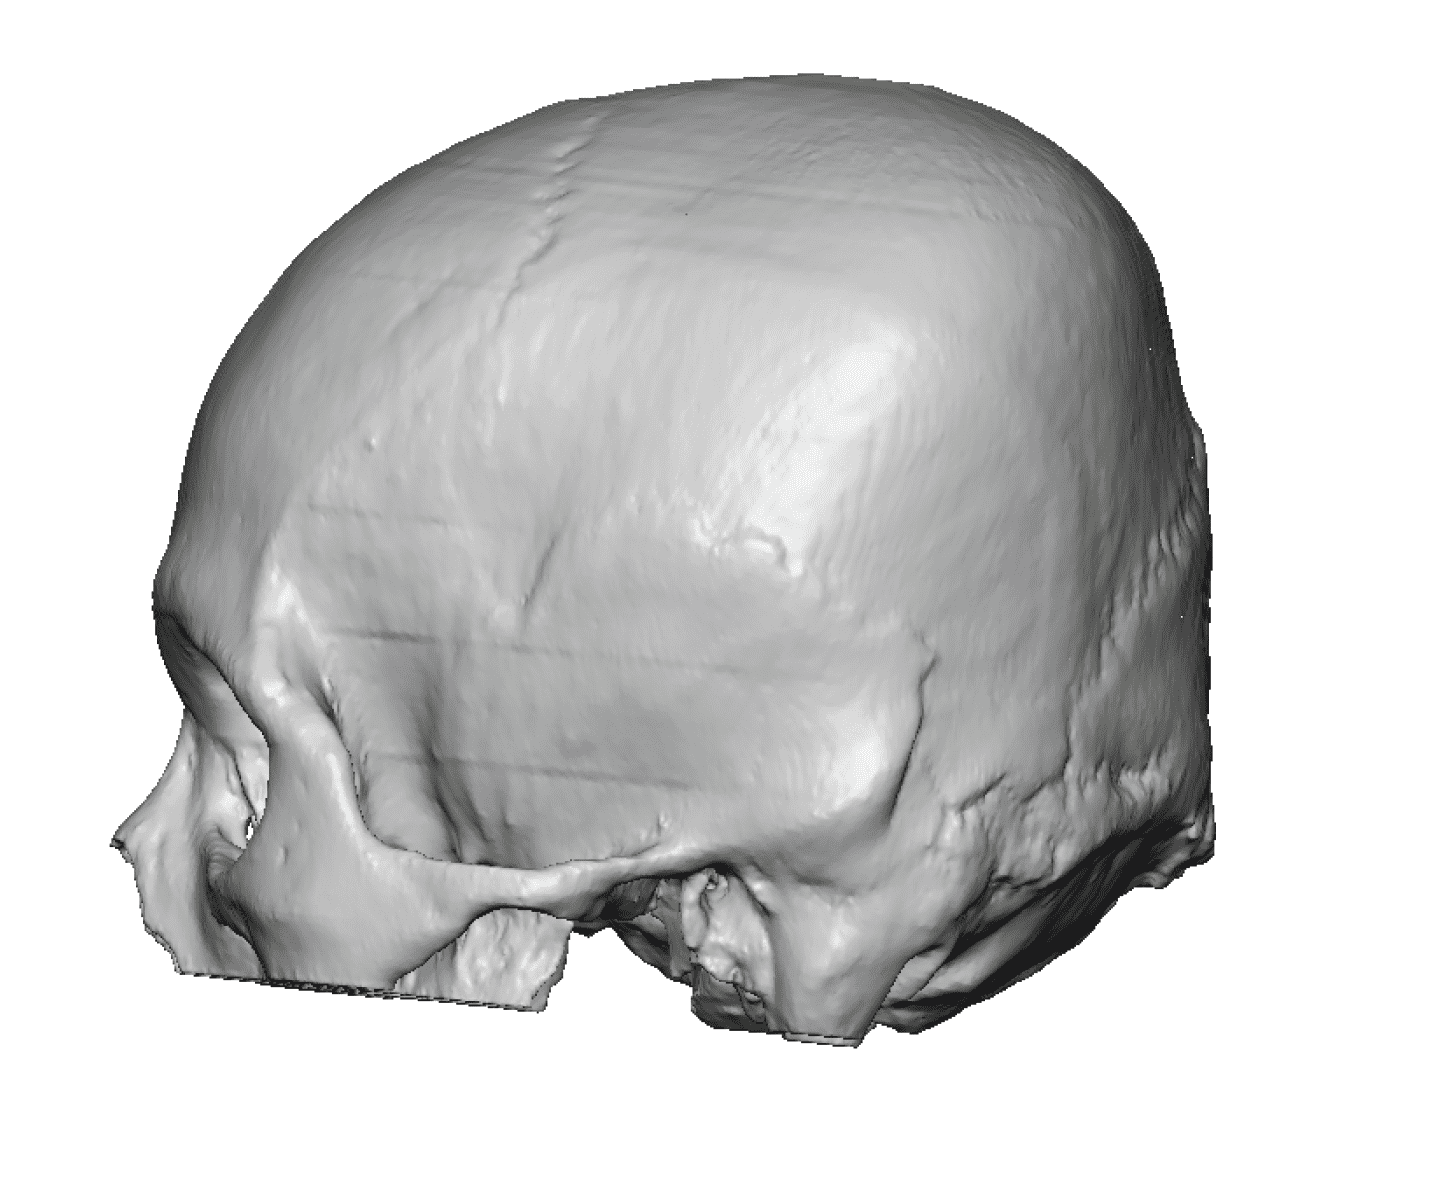

Severe narrowing skull deformity from prior sagittal craniosynostosis repair as an adult.

Complete replacement of entire skull by a custom implant with temporal fat injections.

Severe narrowing skull deformity from prior sagittal craniosynostosis repair as an adult.

Complete replacement of entire skull by a custom implant with temporal fat injections.